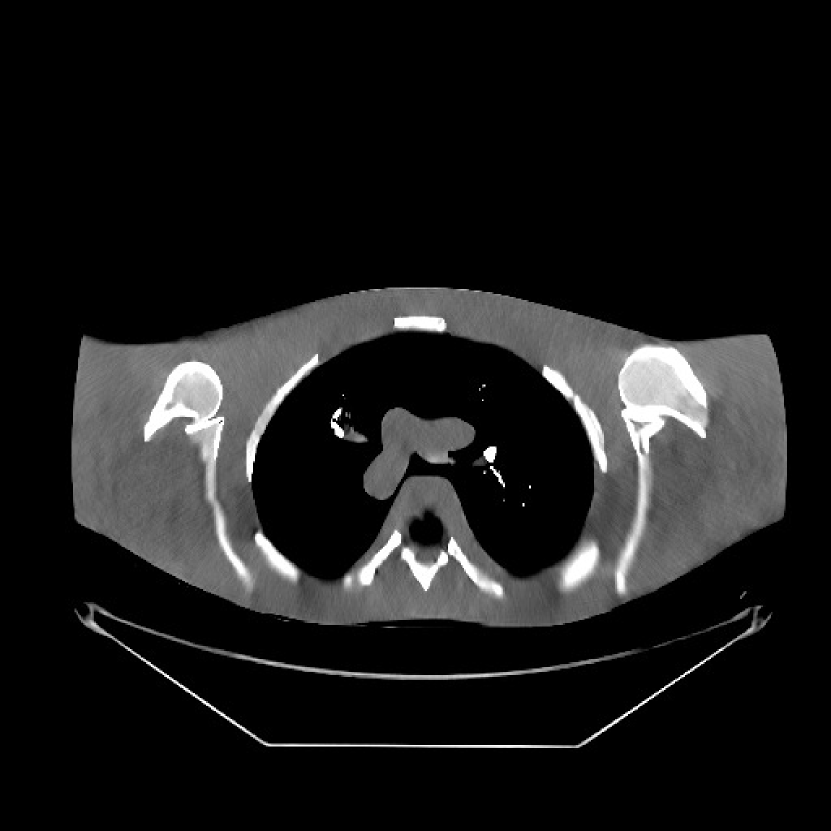

We obtained from GE a 2D fan-beam raw (pre-log) scan of a shoulder phantom, which included the beam-hardening effect. The provided with 1 second scan can be viewed as a standard-dose scan and all the raw measurements are positive. Based on this standard-dose scan, we simulated an ultra low-dose scan as shown in (15) with , and added Poisson and Gaussian noise () to the measurements. The simulated measurements have about non-positive values. The sinograms were of size , and reconstructed images were of size with mm.

For PWLS-ULTRA and SPULTRA, we pre-learned a union of five square transforms using overlapping image patches with stride from five XCAT phantom slices [38]. Here, we also compared SPULTRA with a recent deep-learning based low-dose CT denoising framework “WavResNet” combined with an RNN architecture[46]. The iterative RNN version of WavResNet was pre-trained based on the 2016 Low-Dose CT Grand Challenge data set [46]. During reconstruction, WavResNet, PWLS-ULTRA, and SPULTRA were initialized with the image reconstructed by PWLS-EP with . The parameters for both PWLS-ULTRA and SPULTRA were set as . These values worked well in our experiment. In the supplement, we discuss in detail the parameter selection procedure of for both PWLS-ULTRA and SPULTRA. Parameters for testing WavResNet were set according to [46], and the pixel values of the input to WavResNet were converted to match the network required scalings. Since the WavResNet was trained with images reconstructed with the filtered backprojection (FBP) method [46], we also tested on this shoulder phantom that initialized WavResNet with an FBP reconstructed image. Although initializing WavResNet with an FBP reconstructed image better matches the trained model than the PWLS-EP reconstructed image does, the latter still provided better results. We included in the supplement the denoised image initialized with the FBP reconstruction.

Fig. 10 shows the reconstructions for the scan (reference image) along with the reconstructions for the simulated ultra low-dose scan obtained with PWLS-EP, WavResNet, PWLS-ULTRA, and SPULTRA. Visually, WavResNet fails to reconstruct the image but improves over the initial PWLS-EP reconstruction, while PWLS-ULTRA and SPULTRA provide better image quality. This indicates that the ULTRA-based methods may have a better generalization property than WavResNet, since they learn more fundamental features of CT images (also see [38]). We selected three smooth ROIs, where the pixel values are approximately constant. Tab. V(b) shows the mean and the standard deviation of pixel values for these ROIs for various methods and the standard-dose reference. Since the iterative RNN version of WavResNet only has small improvements over PWLS-EP, the pixel values do not change much compared with PWLS-EP. PWLS-ULTRA however reduces the bias in the central region of the image (ROI 2), but fails to correct the bias in the regions near the bones (ROI 1 and ROI 3). SPULTRA reduces the bias in the central region of the image, and also significantly corrects the bias near the bone regions. The standard deviations of the ROIs reconstructed by SPULTRA are comparable to those reconstructed by PWLS-ULTRA, and are close to those of the reference ROIs. Additionally, SPULTRA reconstructs the bone (indicated by the magenta arrow in the last two subfigures of Fig. 10) better than PWLS-ULTRA.